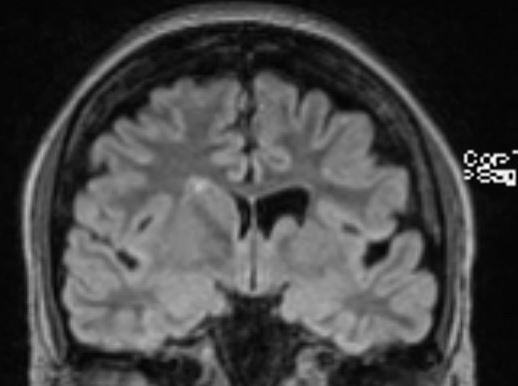

The structural correlates of the above EEG findings appear below. There is enlargement of the left-ventricular system, atrophy of the head, body and tail of the caudate nucleus and the left hemisphere appears modestly smaller in size than the right, most evident on axial sequences. The MRI was done while the patient was quite restless. As you can see from these pictures, the left occipital cortex and the left thalamus do not demonstrate any structural correlate to the asymmetry of alpha rhythms. However, we know from the EEG that the left hemisphere is markedly dysfunctional. Unsurprisingly, on functional MRI scans language is represented in the right hemisphere.